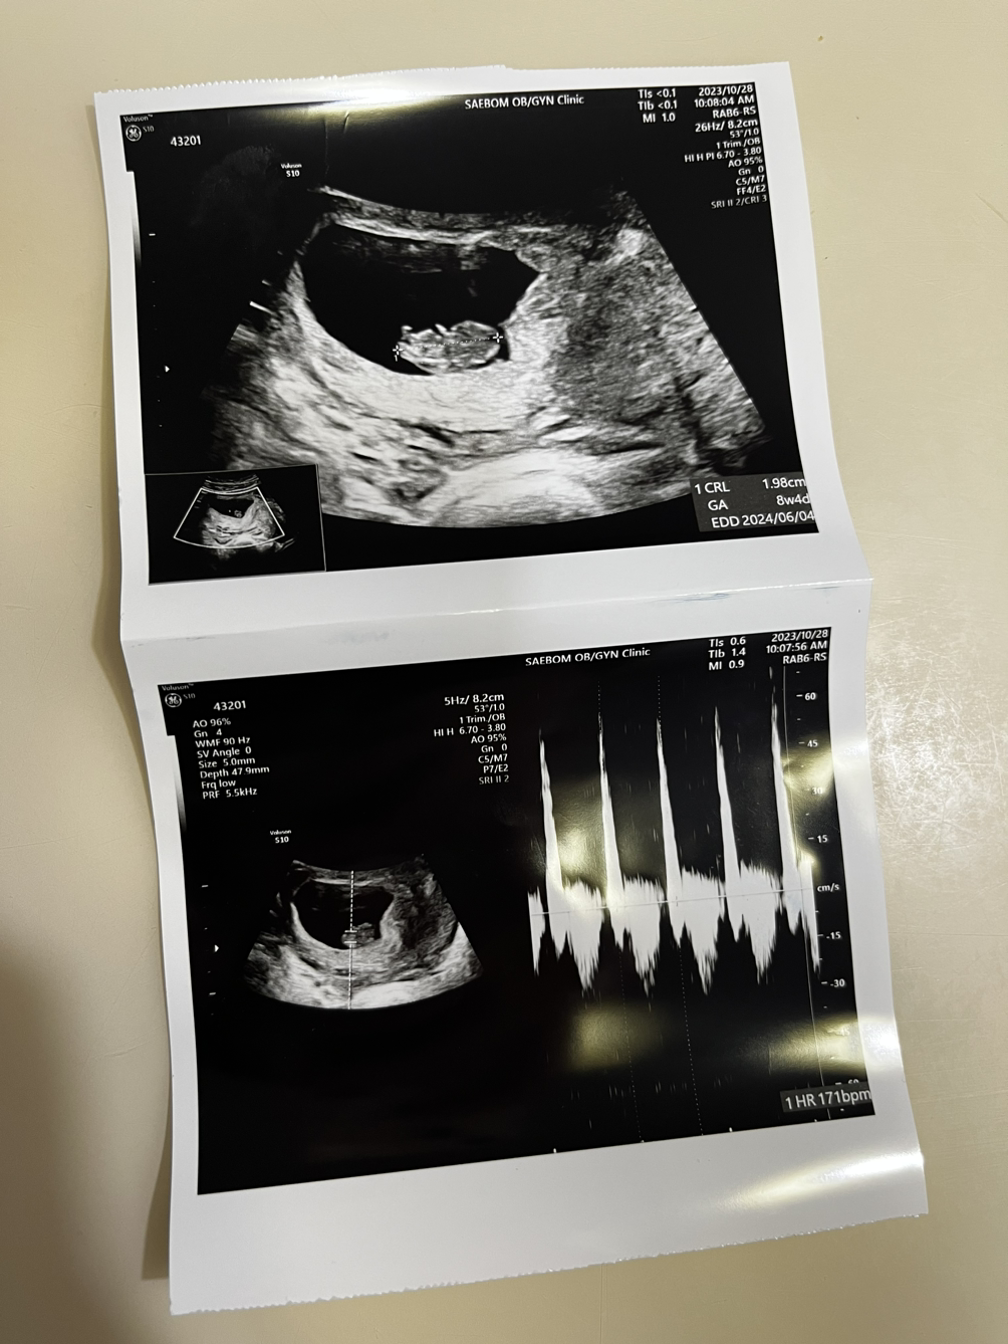

8주 4일이 돼서 태백이는 아빠와 언니 혹은 누나와 처음 만났다. 태백이는 팔다리가 될 부분이 쏙 나와서 사람형체를 띄려고 준비 중이었다. 171bpm으로 열심히 뛰는 심장을 가진 태백이는 1.98cm로 키도 훌쩍 자라 있었다.